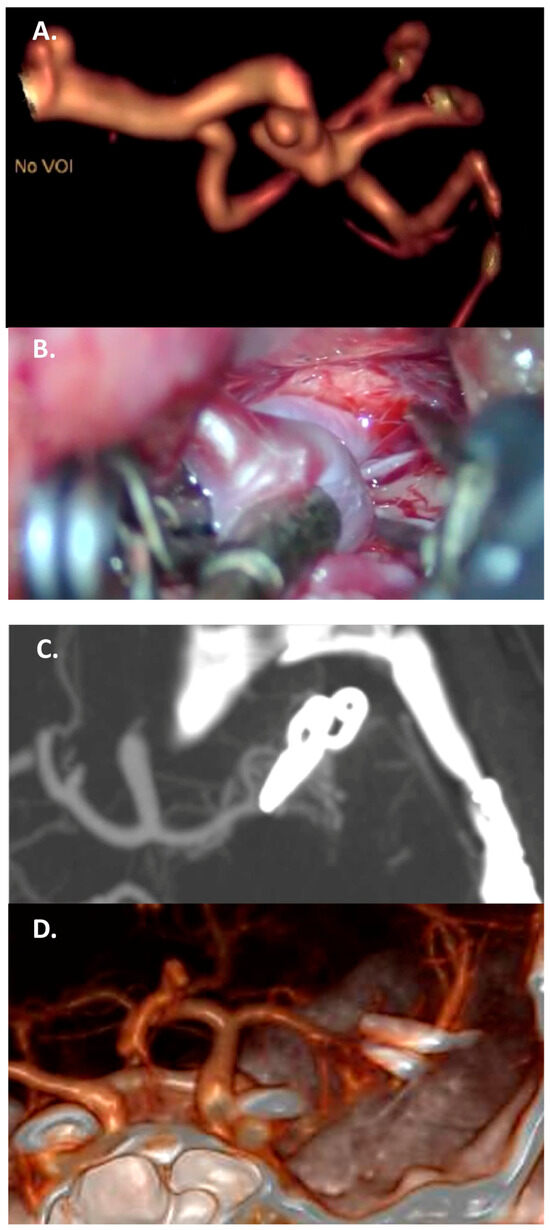

4.3.1. Large/Giant Aneurysm Size and Fusiform Shape

4.3.2. Vessels Branching from the Dome

4.3.3. Thrombosed Aneurysm and/or Previously Treated Aneurysms